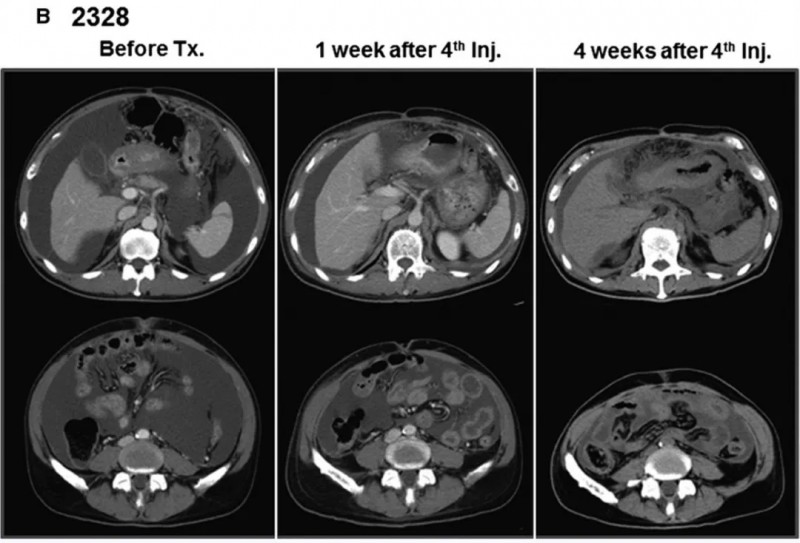

结果显示:2例可评估疗效的患者均获显著治疗反应,临床症状明显缓解:其中患者2328治疗后CT示腹水减少且近乎完全消失(详见下图B),因疗效显著追加两轮输注。

▲图源“WILEY Online Library”,版权归原作者所有,如无意中侵犯了知识产权,请联系我们删除